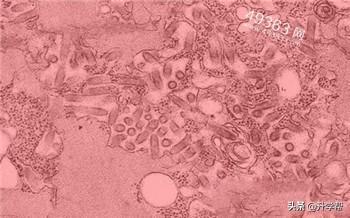

伊波拉(Ebola)是一个用来称呼一群属于纤维病毒科伊波拉病毒属下数种病毒的通用术语,可导致伊波拉病毒出血热,罹患此病可致人于死,包含数种不同程度的症状。

包括恶心、呕吐、腹泻、肤色改变、全身酸痛、体内出血、体外出血、发烧等,感染者症状与同为纤维病毒科的马尔堡病毒极为相似。具有50%至90%的致死率,致死原因主要为中风、心肌梗塞、低血容量休克或多发性器官衰竭。

此病毒以非洲刚果民主共和国的伊波拉河命名(该国旧称萨伊),此地接近首次爆发的部落,刚果仍是最近四次爆发的所在地,包括2005年5月的一次大流行。伊波拉病毒是人畜共通病毒,通常借由体液、黏膜、皮肤等接触造成感染。

尽管世界卫生组织苦心研究,至今仍没有辨认出任何有能力在爆发时存活的动物宿主,目前认为果蝠是病毒可能的原宿主。因为伊波拉病毒的致命力,加上目前尚未有任何疫苗被证实有效,伊波拉病毒被列为生物安全第四级病毒,也同时被视为是生物恐怖主义的工具之一。